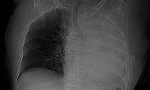

Bệnh nhi nhập viện trong tình trạng ho sặc sụa, khó thở, thông khí phổi giảm 2 bên. Các bác sĩ đã thăm khám lâm sàng, nghi ngờ trẻ bị hóc dị vật đường hô hấp.

Qua khai thác, bệnh nhi đã ngậm bút trong miệng và vô tình rơi đầu ngòi bút vào đường thở lúc học tập. Bệnh nhi được chỉ định chụp CT ngực, kết quả ghi nhận dị vật hình ống, bề dày thành khoảng 1,8mm, chiều dài khoảng 18mm, nằm tại phế quản thùy dưới trái, gây cản trở thông khí.

Sau hội chẩn chuyên khoa, bệnh nhi được chỉ định nội soi phế quản cấp cứu lấy dị vật. Các bác sĩ đã lấy ra dị vật là đầu ngòi bút nhựa. Sau thủ thuật, tình trạng hô hấp của trẻ cải thiện rõ rệt và tiếp tục được theo dõi, điều trị tại bệnh viện.